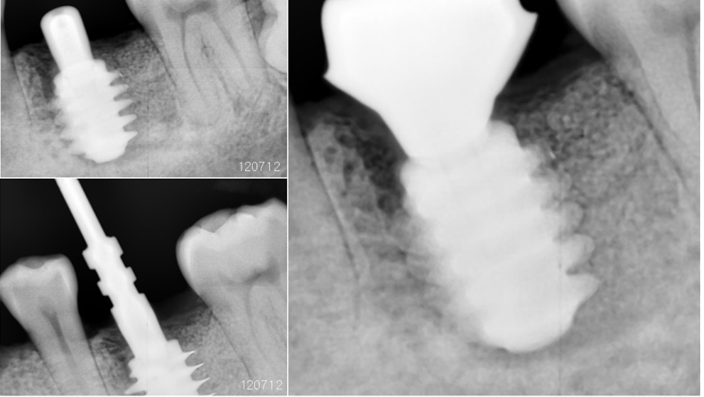

Clinical case: Bone filling into the bottom of deepest thread at 8.0mm AnyRidge fixture

- Courtesy of Dr. Kwang Bum Park -

Keywords

AnyRidge, Knifethread ,extraction socket, ,initial stability ,Allograft, ,osseointegratio ,Dr. Kwang Bum Park, , Mandibular, Single replacement, AnyRidge, Mega-oss,

Products used

Implant system-AnyRidge, Regeneration-Mega-Oss

How can primary stability be increased?

Primary stability is especially important in the case of poor quality bone. The instability of dental implants results in fibrous encapsulation and failed osseointegration (Lioubavina-Hack, et al. 2006). One method for increasing primary stability is modifying the surgical technique for implant placement. Studies have reported that the undersized surgical technique, which uses a final drill diameter smaller than the diameter of the implant, results in a higher primary stability when compared with the press-fit technique (Tabassum, et al. 2009, Tabassum, et al. 2010a).

Other studies have reported a higher implant stability with the bone-condensing techniques rather than the bone-drilling technique (Fanuscu, et al. 2007, Markovic, et al. 2011) and conventional techniques rather than the osteotome technique (Cehreli, et al. 2009, Padmanabhan, et al. 2010). The stress distribution of Ti implants with various thread depths has also been investigated using finite element analyses(FEA) to identify the most effective thread depth for stress distribution (Ao, et al. 2010, Chun, et al. 2002, Kong, et al. 2008).

The thread depth also provides a higher contribution than the thread width for stress distribution to the bone (Kong, et al. 2008).

Ti implants with a deeper thread depth provide a higher surface area, which is advantageous for increasing stability in areas of poor quality bone (Abuhussein, et al. 2010). Ti implants with deeper thread depths also facilitate an increased load and mechanical interlocking with poor quality bone.